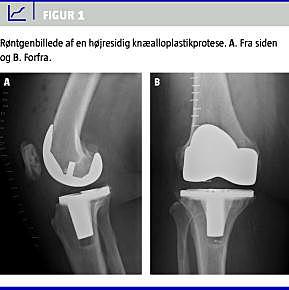

En 66-årig kvinde med kendt kronisk obstruktiv lungesygdom fik foretaget en højresidig TKA på grund af svær artrose (Figur 1 ). Hun havde ikke vaskulær insufficiens og fik ingen former for antikoagulansbehandling.